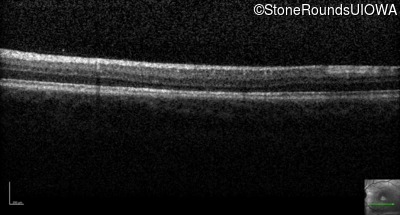

Optical Coherence Tomography - Right - 20/40 -2

Exemplar / OCT Stack